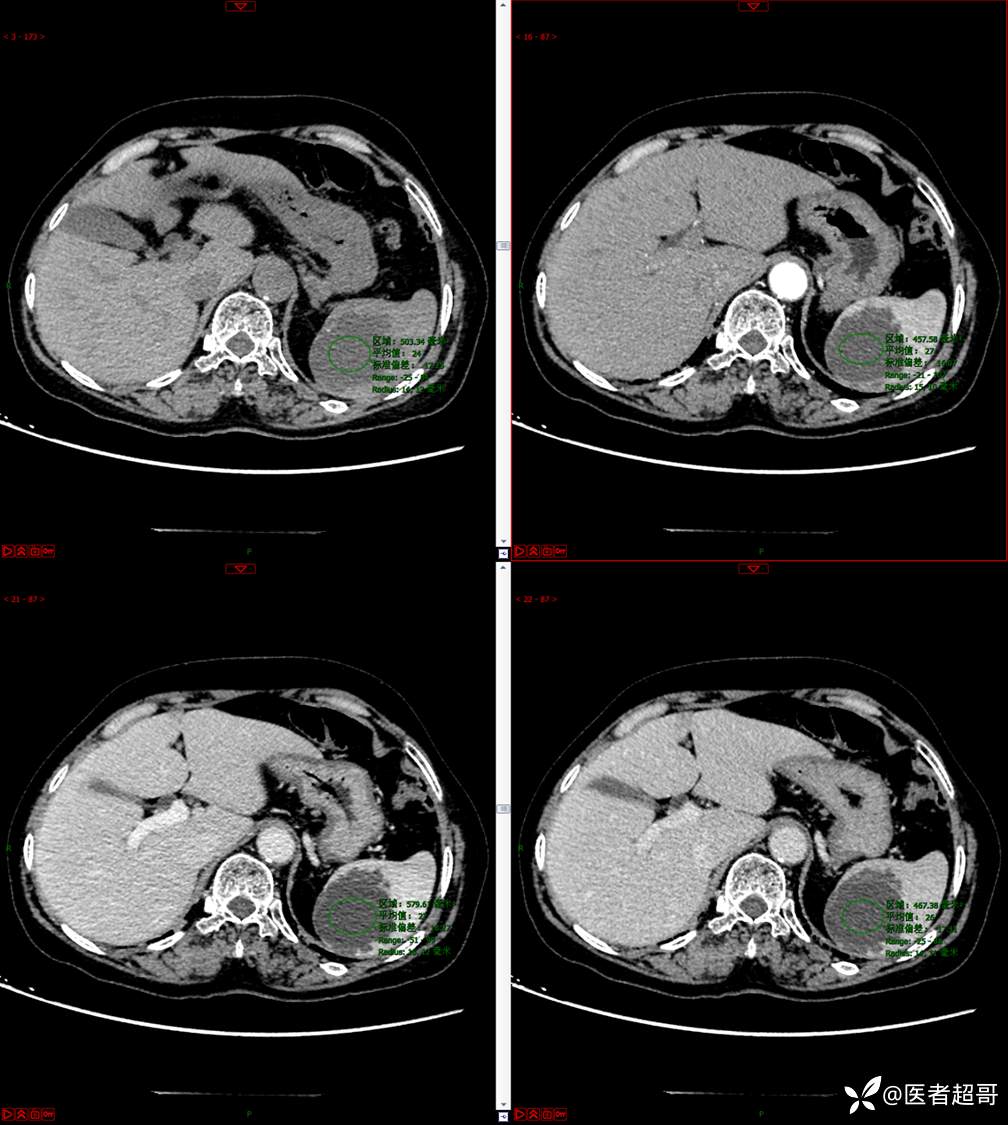

现病史:患者9天前于市人民医院查体时发现脾脏肿物,未行处理,后于我院门诊查,上腹部CT平扫+强化:脾脏占位,考虑良性,囊肿?脉管源性病变?患者诉平素无异常不适。现患者为求进一步诊疗,门诊遂以“脾肿物”收入院。患者自患病以来,神志清,精神可,饮食、睡眠可,大小便正常,体重未见明显变化。